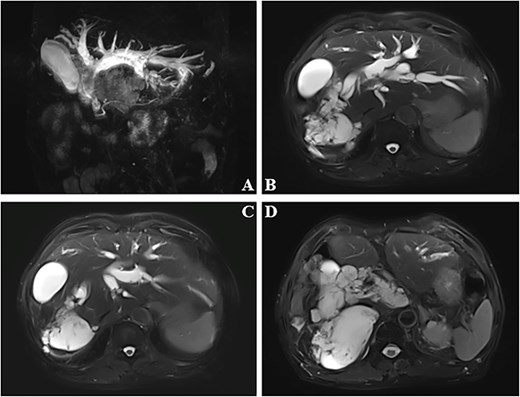

A 76-year-old elderly male was admitted to our hospital due to jaundice (icterus of the skin and sclera) persisting for over one month. One month prior, he presented to a local hospital with jaundice. An upper abdominal contrast-enhanced magnetic resonance imaging (MRI) scan plus magnetic resonance cholangiopancreatography revealed a space-occupying lesion in the right hepatic lobe and hepatic hilum, suggestive of cystadenoma, with cholangiocarcinoma not excluded. Intra- and extrahepatic bile duct stones were noted with concomitant biliary duct dilation. The gallbladder was slightly enlarged, with an abnormal signal focus within its lumen; possible sludge stones, or inflammatory sediment (Fig. 1)? Tumor markers, including CA125, CA199, AFP, and PIVKA-II, were all within normal ranges. During his hospitalization there, supportive treatment including jaundice reduction, liver protection, and nutritional support was administered, but his symptoms showed no significant improvement.

Dilated bile ducts (A). The mass shows high signal intensity on MRI T2-weighted images (B–D).